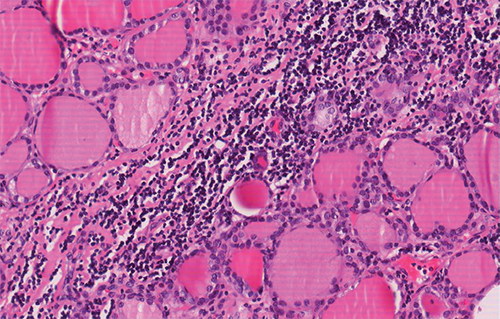

Las secciones microscópicas estudiadas en el lóbulo derecho exclusivamente muestran un parénquima tiroideo infiltrado por un tejido fibrocolágeno acompañado de un infiltrado inflamatorio constituido principalmente por linfocitos y algunas células plasmáticas, sin evidencia de formación de folículos linfoides. El parénquima tiroideo conservado presenta focos de atrofia folicular tiroidea. Además, dicha fibrosis e inflamación se extiende a tejido adiposo y muscular estriado adyacente. El lóbulo izquierdo no presenta alteraciones histopatológicas significativas (Figura 2); siendo todo ello compatible con el diagnóstico de tiroiditis fibrosante de Riedel con afectación unilateral (lóbulo tiroideo derecho).

Figura 2. A: Se observan folículos tiroideos del parenquima normal con un área adyacente de inflamación crónica linfoplamocitaria infiltrante. 20x H-E.

Figura 2. B: Se observan un área de fibrosis colágena e inflamación crónica linfoplasmocitaria sin foliculos linfoides, infiltrando el parenquima tiroideo y atrofiandolo

focalmente. 0.9x H-E.